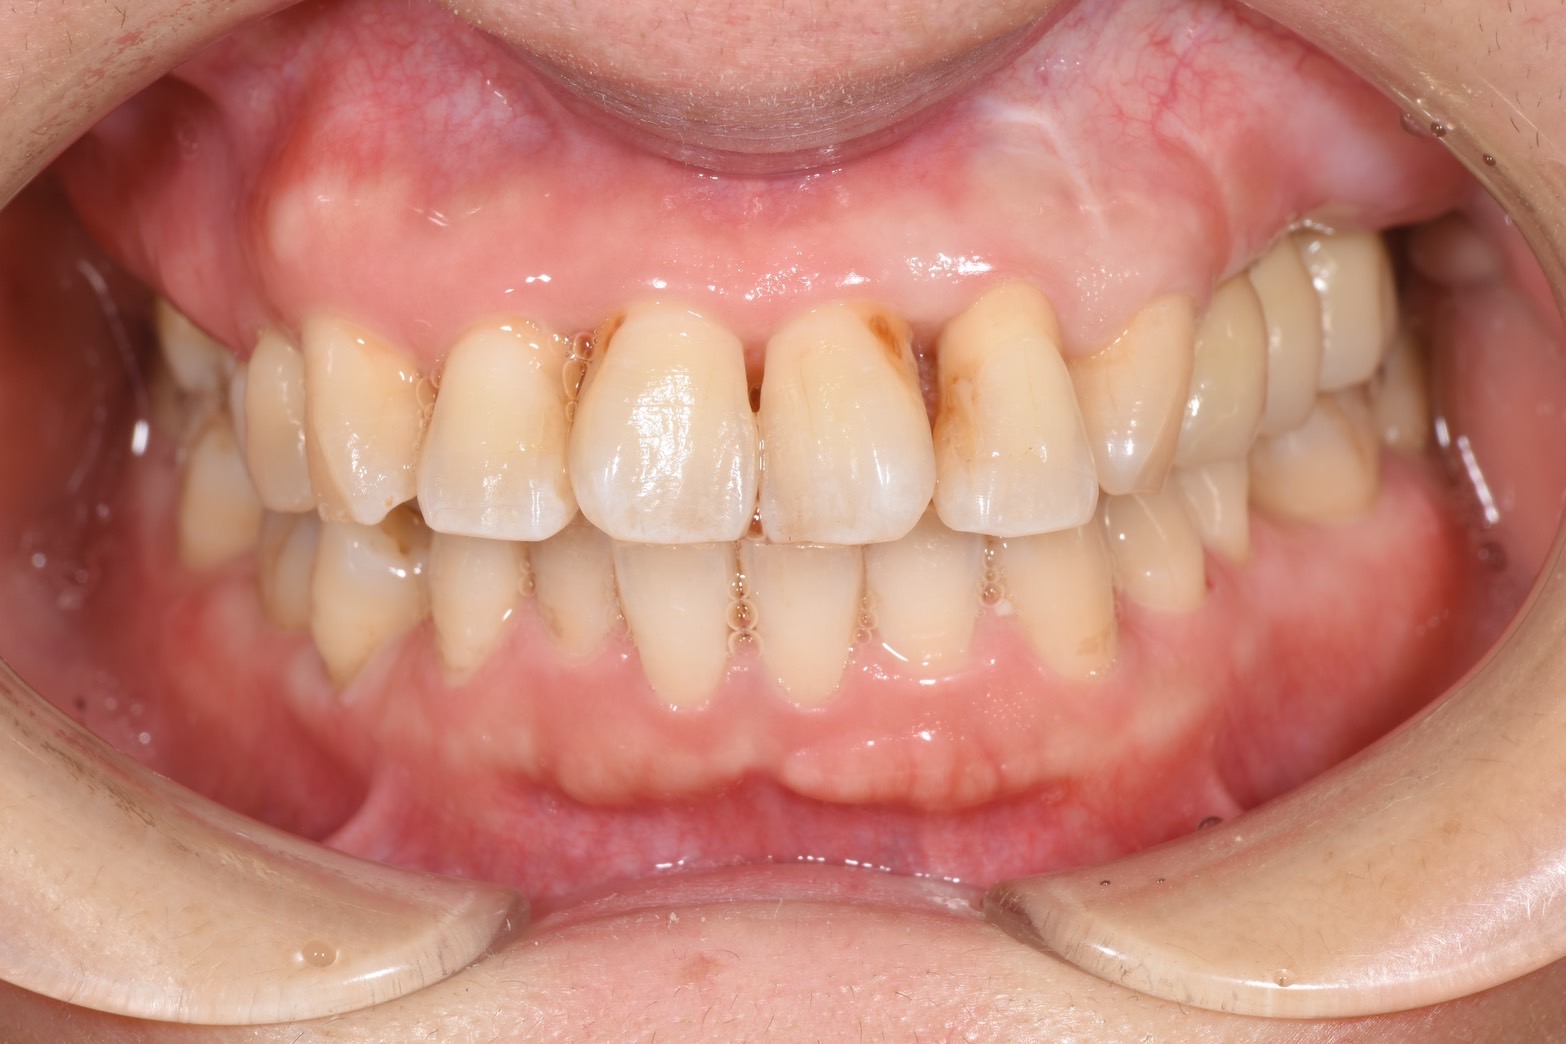

Before

歯周病によって骨が無くなり、インプラントができない状態であったため、骨造成してインプラント治療を行いました。